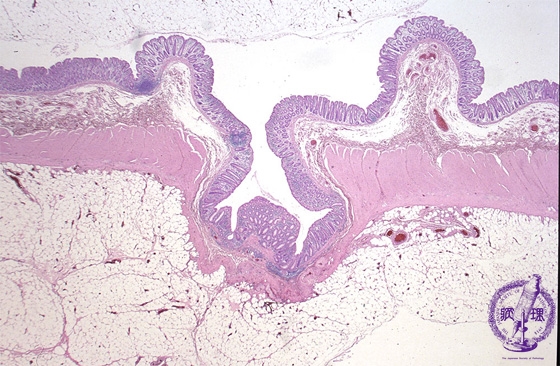

- 9.Small intestine, Large intestine

- (2)Diverticulosis of large intestine (diverticulitis) >

Microscopic view (H&E stain, low power): Both mucosa and the underlying muscularis propria protrude through the external bowel wall.

Click the image to see the enlarged image.